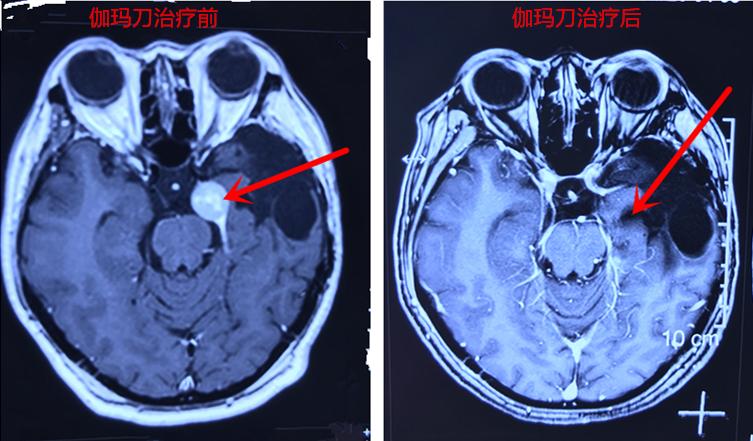

患者女性,44岁,脑膜瘤术后5年余复发,近两月头痛行头颅MRI检查提示:右侧小脑半球近小脑幕旁稍高信号影,大小1.6×1.7cm,边界清,与小脑幕以宽基地相贴,增强后明显强化,相邻小脑幕增厚、强化,考虑脑膜瘤术后复发。

患者及家属不愿意再次开颅手术,了解到伽玛刀治疗无外科手术风险、麻醉风险等,遂入我院伽玛刀诊疗中心,通过核磁共振增强扫描定位:明确以右侧小脑病灶为本次治疗靶区,治疗靶区病灶大小为:1.5×1.8×2.0cm,以50%等剂量曲线包绕靶区,治疗周边剂量1550cGy,中心剂量为3100cGy,治疗时间26分钟。术后1年随访发现肿瘤明显缩小。